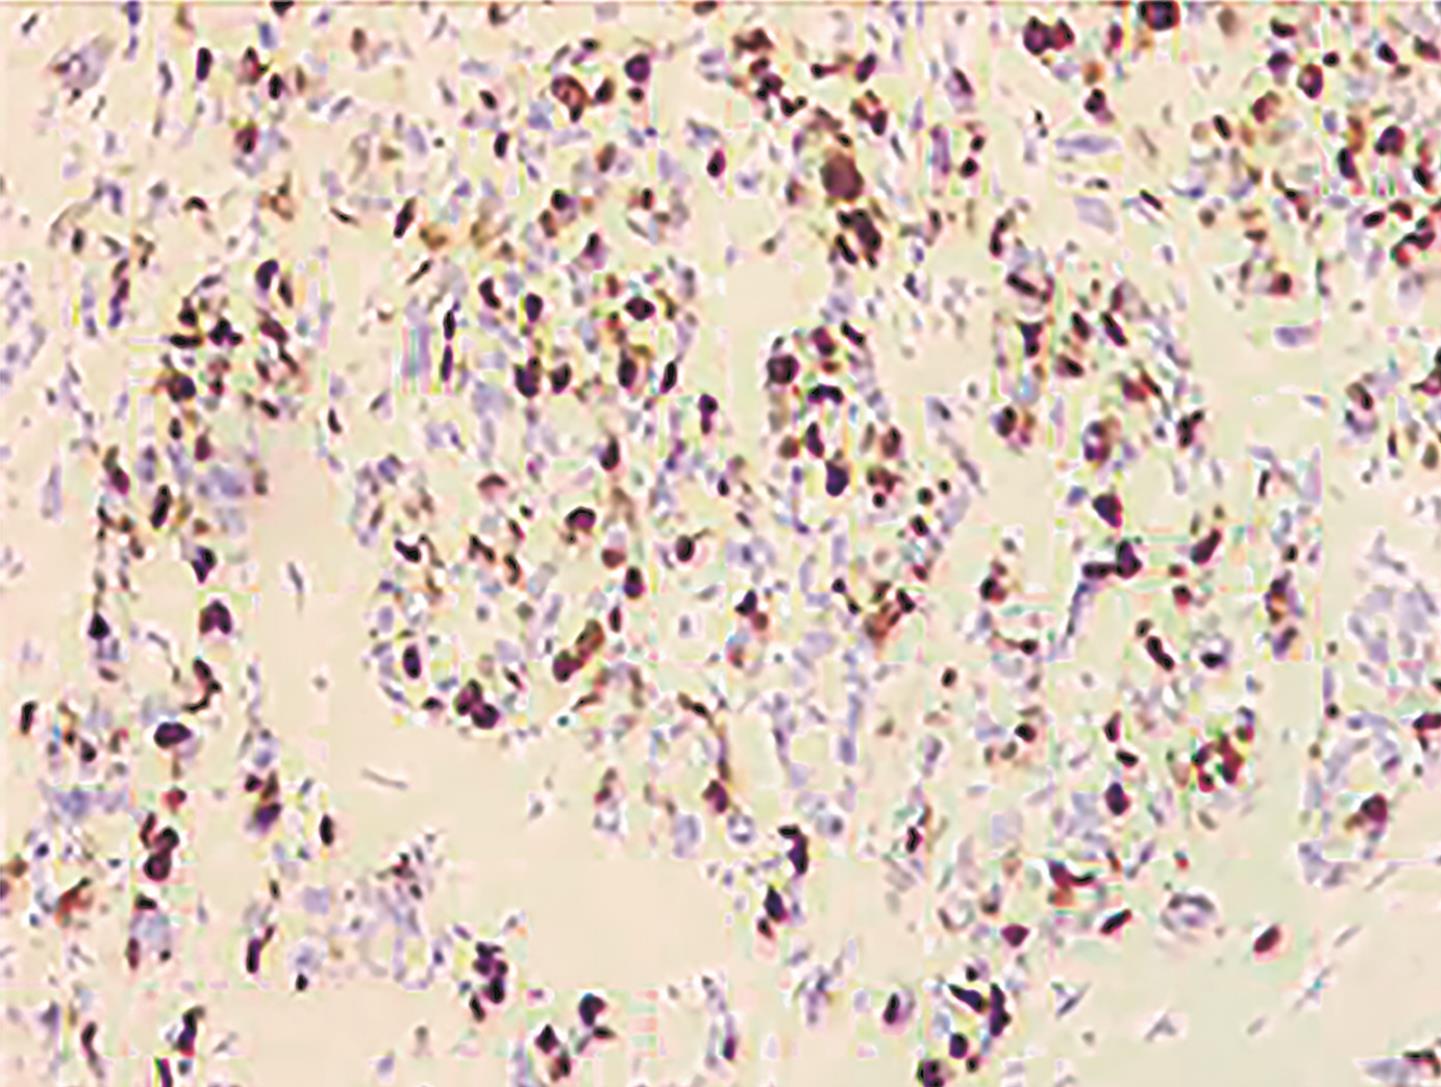

• 胆囊腺癌伴印戒细胞癌1例

摘要: